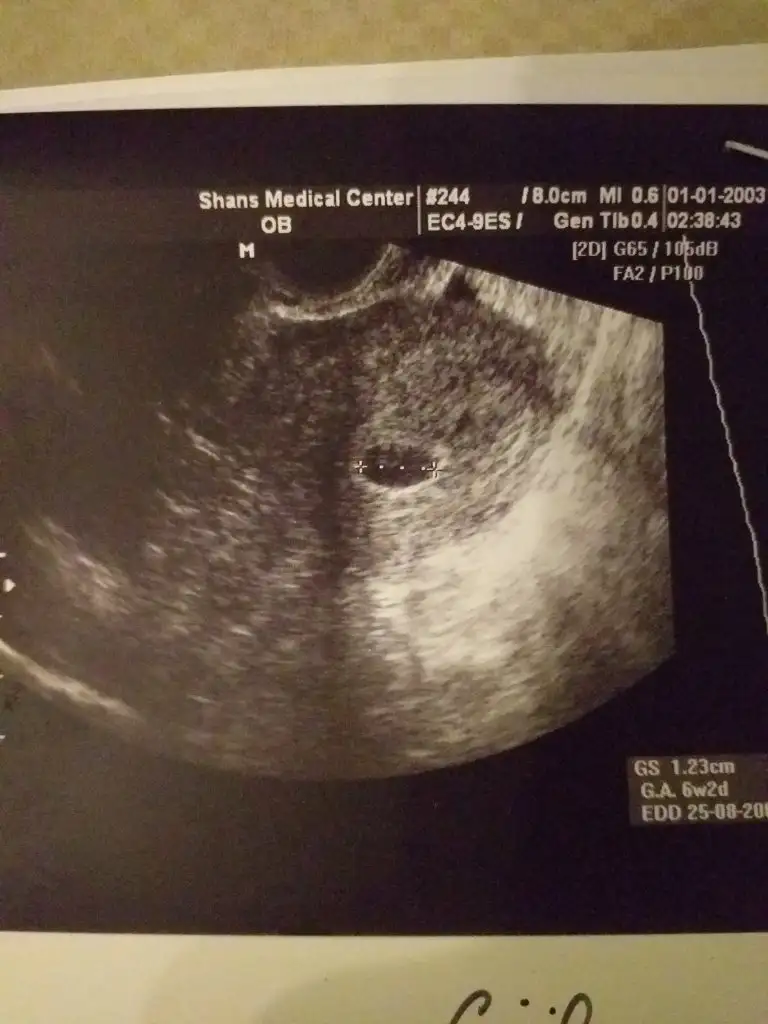

Bu benim 5.hafta vajinal ultrasonum ilk fotoğraftaki. altta 6. hafta diyor ama benim 1 hafta geç döllenme.

2.foto 6.hafta karından ultrason.

tahmininiz nedir?